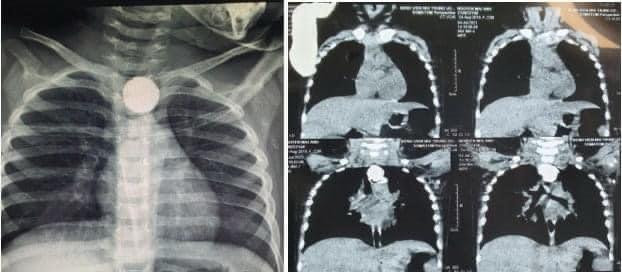

BS. Nguyễn Minh Khôi - Khoa Ngoại tổng hợp, Bệnh viện Nhi Trung ương - cho biết: Trẻ nhập viện trong tình trạng nhiễm trùng (sốt 39 độ, môi khô, lưỡi bẩn) và suy hô hấp (thở nhanh nông, rút lõm lồng ngực). Vì thế, các bác sĩ đã chỉ định chụp X-quang và chụp cắt lớp vi tính ngực (chụp CT) cho trẻ. Kết qủa, các bác sĩ phát hiện hình ảnh dị vật cản quang hình tròn nằm tại thực quản ngực của trẻ. Nếu không được phẫu thuật kịp thời thì tình trạng nhiễm trùng sẽ lan rộng, áp-xe trung thất, nhiễm trùng huyết gây nguy hiểm đến tính mạng. Các bác sĩ đã ổn định huyết động cho bé, hỗ trợ hô hấp bằng oxy mask, dùng kháng sinh và chỉ định phẫu thuật nội soi tiêu hoá kiểm tra và lấy dị vật.

| Hình ảnh chụp Xquang của bệnh nhi (Ảnh - BVCC) |